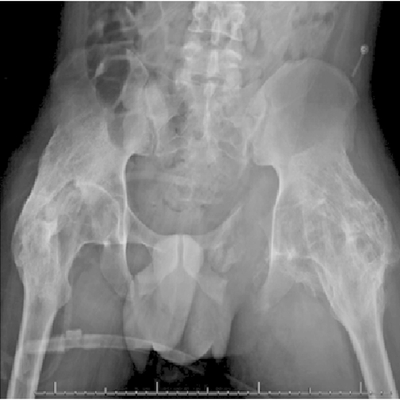

Click on an image below to view more info.